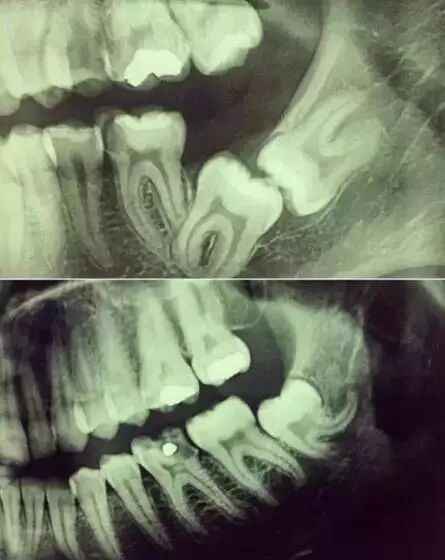

小牙片(根尖片)

小牙片主要是拍摄单颗牙,可以了解牙齿龋坏程度,根尖周的病变情况,牙周骨质破坏情况等。但是在口腔颌面外科不常用。